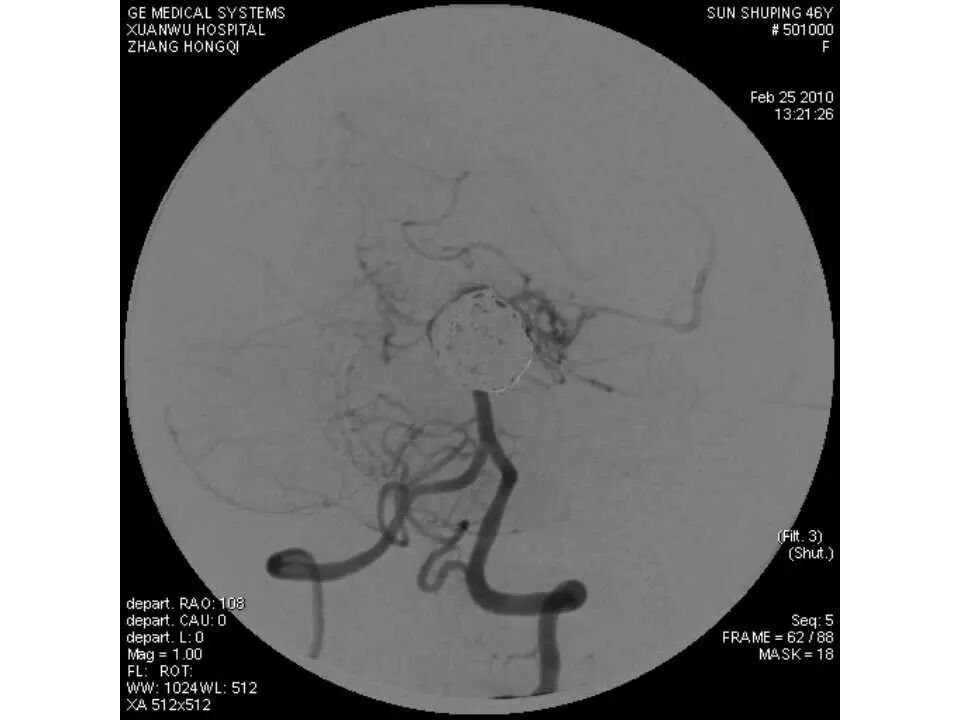

今天为大家分享的是“强生医疗CNV-神经介入专栏”第十五期,由首都医科大学宣武医院何川教授带来的“颅内动脉瘤介入治疗”精彩讲课视频及PPT,欢迎观看、阅读。文章仅代表作者个人观点,如有不同见解,欢迎同道斧正!

何川 ,首都医科大学宣武医院副主任医师,中国医师协会神经介入专业委员会常务委员,长期从事脑血管病和脊髓血管病的手术及介入治疗和相关研究工作。首都医科大学神经外科博士,师从于中国神经介入开创人凌锋教授;日本东北大学医院脑血管病治疗科博士后,师从于日本国脑血管病血管内治疗的开创者高桥教授。